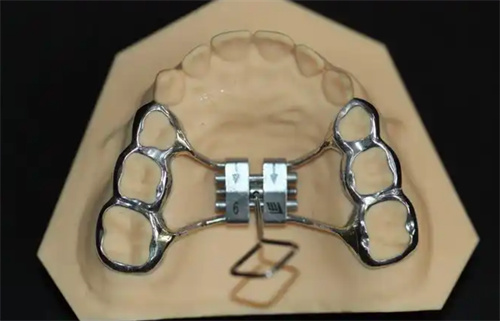

MSE(Maxillary Skeletal Expander)上颌骨骨性扩弓器,作为一种新型的正畸治疗工具,近年来在口腔医学领域受到了广泛关注。

它由美国UCLA大学的Dr. Moon医师发明,主要用于解决上颌横向发育不足(牙弓狭窄)的问题,尤其适用于青春发育期后及腭中缝已经闭合的成人患者。

MSE扩弓器通过微种植钉辅助,实现了对上颌骨的快速扩展,为患者带来了显著的治疗结果。

与传统的Hyrax扩弓器相比,MSE扩弓器对牙槽骨的影响较小,不会导致明显的牙根长度变化或牙槽骨吸收。这使得MSE扩弓器在治疗过程中更加安心、可靠。

MSE扩弓器的设计较为简单,操作方便。它的加力过程需要遵循一定的时间表和力度要求,但总体上不需要复杂的外科手术,减少了患者的痛苦和改善时间。